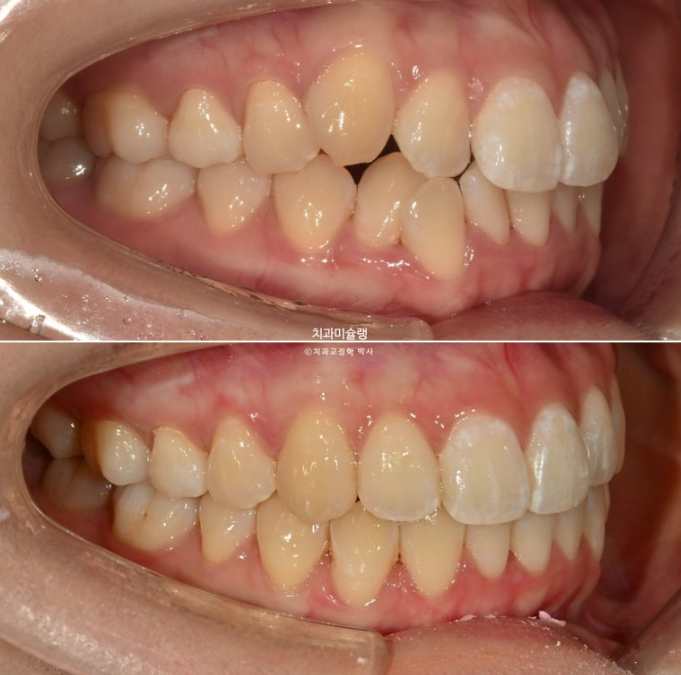

비발치로 충분히 가능하고 입매의 문제도 없는데도 불구하고 타치과에서 발치교정 진단을 받고 온 환자분입니다.

오늘은 비발치 교정 사랑니 공간을 이용하여 덧니와 중심선, 가위교합을 개선한 증례를 보여드리겠습니다.

중심선이 약 3mm 어긋나 있습니다.

덧니가 보이고 파란화살표에 소구치에 가위교합도 있습니다.

발치가 필요할 정도의 덧니나 돌출입은 아니여서 비발치로 매복된 사랑니를 빼고 사랑니 공간을 이용하여 어금니를 뒤로 이동 시키는 치료를 권유드렸습니다.

개선된 덧니와 가위교합